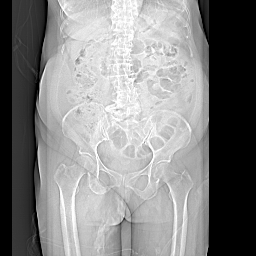

以下是引用余辉在2008-11-9 9:47:00的发言:[br]各层面均可见降结肠管壁增厚,管腔狭窄,中部层面可见管壁明显增厚区,结合病史多考虑降结肠癌,溃疡性结肠炎不除外,建议进一步检查